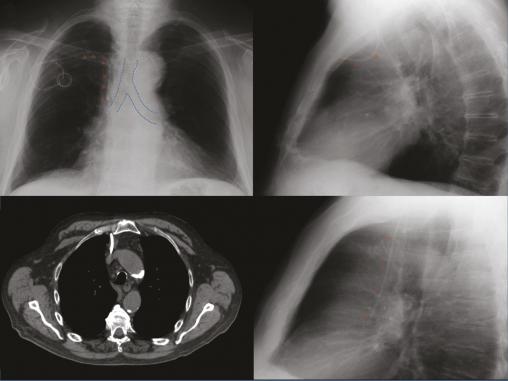

Chez ce patient, une radiographie de thorax était demandée pour contrôler la position d’un cathéter veineux central avec chambre implantable. Sur le cliché de face (fig. 1A ), l’extrémité distale du cathéter pouvait sembler correctement positionnée, mais le cliché de profil (fig. 1B ) montrait une anomalie évidente de trajectoire. La tomodensitométrie (fig. 2 ) confirmait la malposition du cathéter au sein du médiastin antérieur. Pour exemple, la figure 3 montre le trajet d’un cathéter vertical normal vu de profil. Cet exemple montre l’intérêt d’un cliché de profil systématique lors du contrôle de la position d’un cathéter.